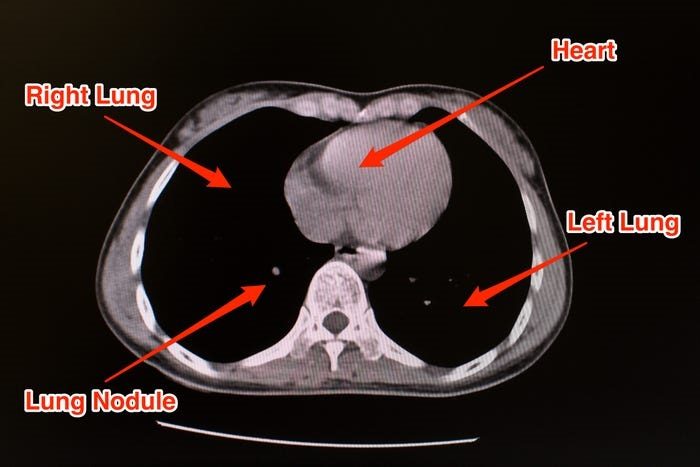

ينبغي أن تظهر الرئة السليمة باللون الأسود في الفحص بالتصوير المقطعي المحوسب، إذ من الشائع وجود كتل صغيرة من الأنسجة أو العقيدات الرئوية التي تبدو في هيئة نقاط بيضاء.

لكن في فحوص تشخيص فيروس كورونا، تبدو صور الأشعة بها بقع بيضاء اللون يسمّيها أخصائيو الأشعّة ground glass opacity "عتامة الزجاج المُصنفر".

باراس لاكاني، أخصائي الأشعة في جامعة توماس جيفرسون، لموقع Business Insider، قال: "يبدو الأمر كأنه زجاج باهت مُصنفر، ويجسّد وجود سائل في مساحة الرئة". ولكن باراس قال أيضاً إن هذه العتامة الزجاجية ليست كافية وحدها لتشخيص فيروس كورونا.